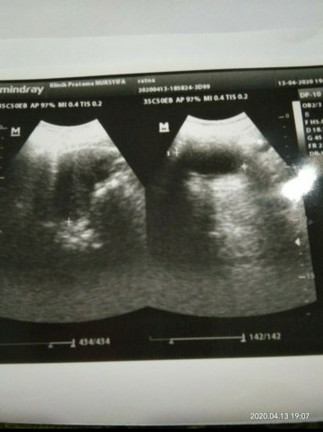

Ini usia kandungan 3 buln,, apakah aku benar" hamil.???

Apakah aku benar" hmil.???

Kayaknya itu kosong deh bun. Bunda gak tanyakan ke dokter kandungan saat periksa gak?

Kata dokterny gmn

Brti bnrn hml dong